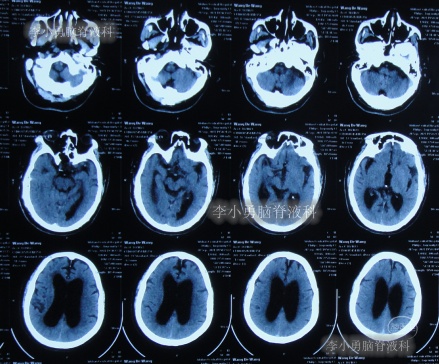

2021年4月14日(腰大池腹腔分流术后17天),头痛腿沉再次加重,复查头部CT示硬膜下血肿(图-3)。

图-3:2021年4月14日头部CT

2021年4月16日(腰大池腹腔分流术后19天),因意识变差,查头部CT(图-4)后,急诊进行了硬膜下血肿引流术,并升高分流泵的压力200。

图-4:2021年4月16日头部CT